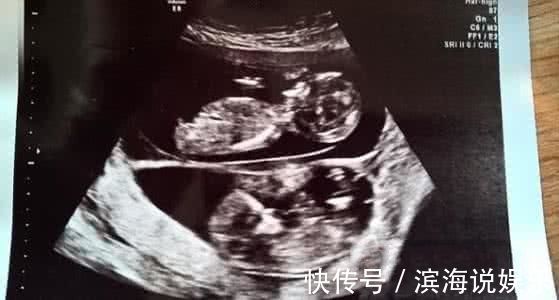

在美国阿肯色州,一名孕妇在怀孕五个月后例行超声波检查时令医生大吃一惊,因为医生们发现该名孕妇在腹中的女婴旁边,再怀有一名胎龄更小的男婴。

据社交媒体报道,阿肯色州KFSM-TV电视台接获的声明指出,相信格罗文伯格太太是在怀有女婴吉莉恩整整五个月后才怀有男婴赫德森的。 妇产科医生迈克尔说:“这种情况很少见,但存在这种可能性。我们得等婴儿出生,给他们做染色体等检测后才能确定。”